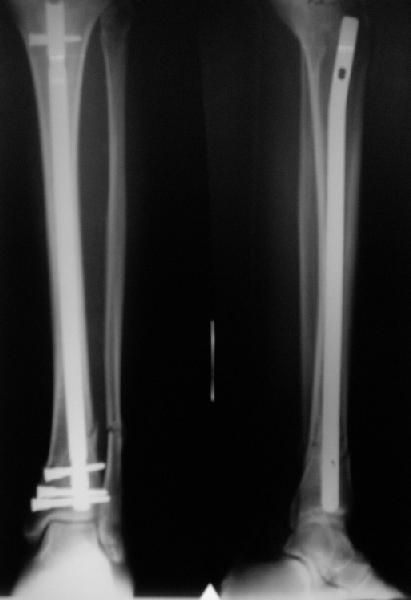

A typical case is attached, also an image with intra-op reduction obtained by a small wire distractor, in the moment of insertion a Poller wire in AP direction. Fixation by a SIGN nail. Despite the fibula was not fixed healing was obtained with the unchanged alignment.

Very interesting application, but is the final position in a little distal varus with some fibula

distraction? Would that have been eliminated by fibula plating?

At least both the ankle mortise and tibial alignment look acceptable, don't they?

I am just trying to illustrate that prevention of 1)tibial valgus and 2)loss of reduction can be provided without fibular plating. Small changes of conventional nailing techniques allow to maintain reduction of the tibia reliably without adjunctive fibular stabilization.